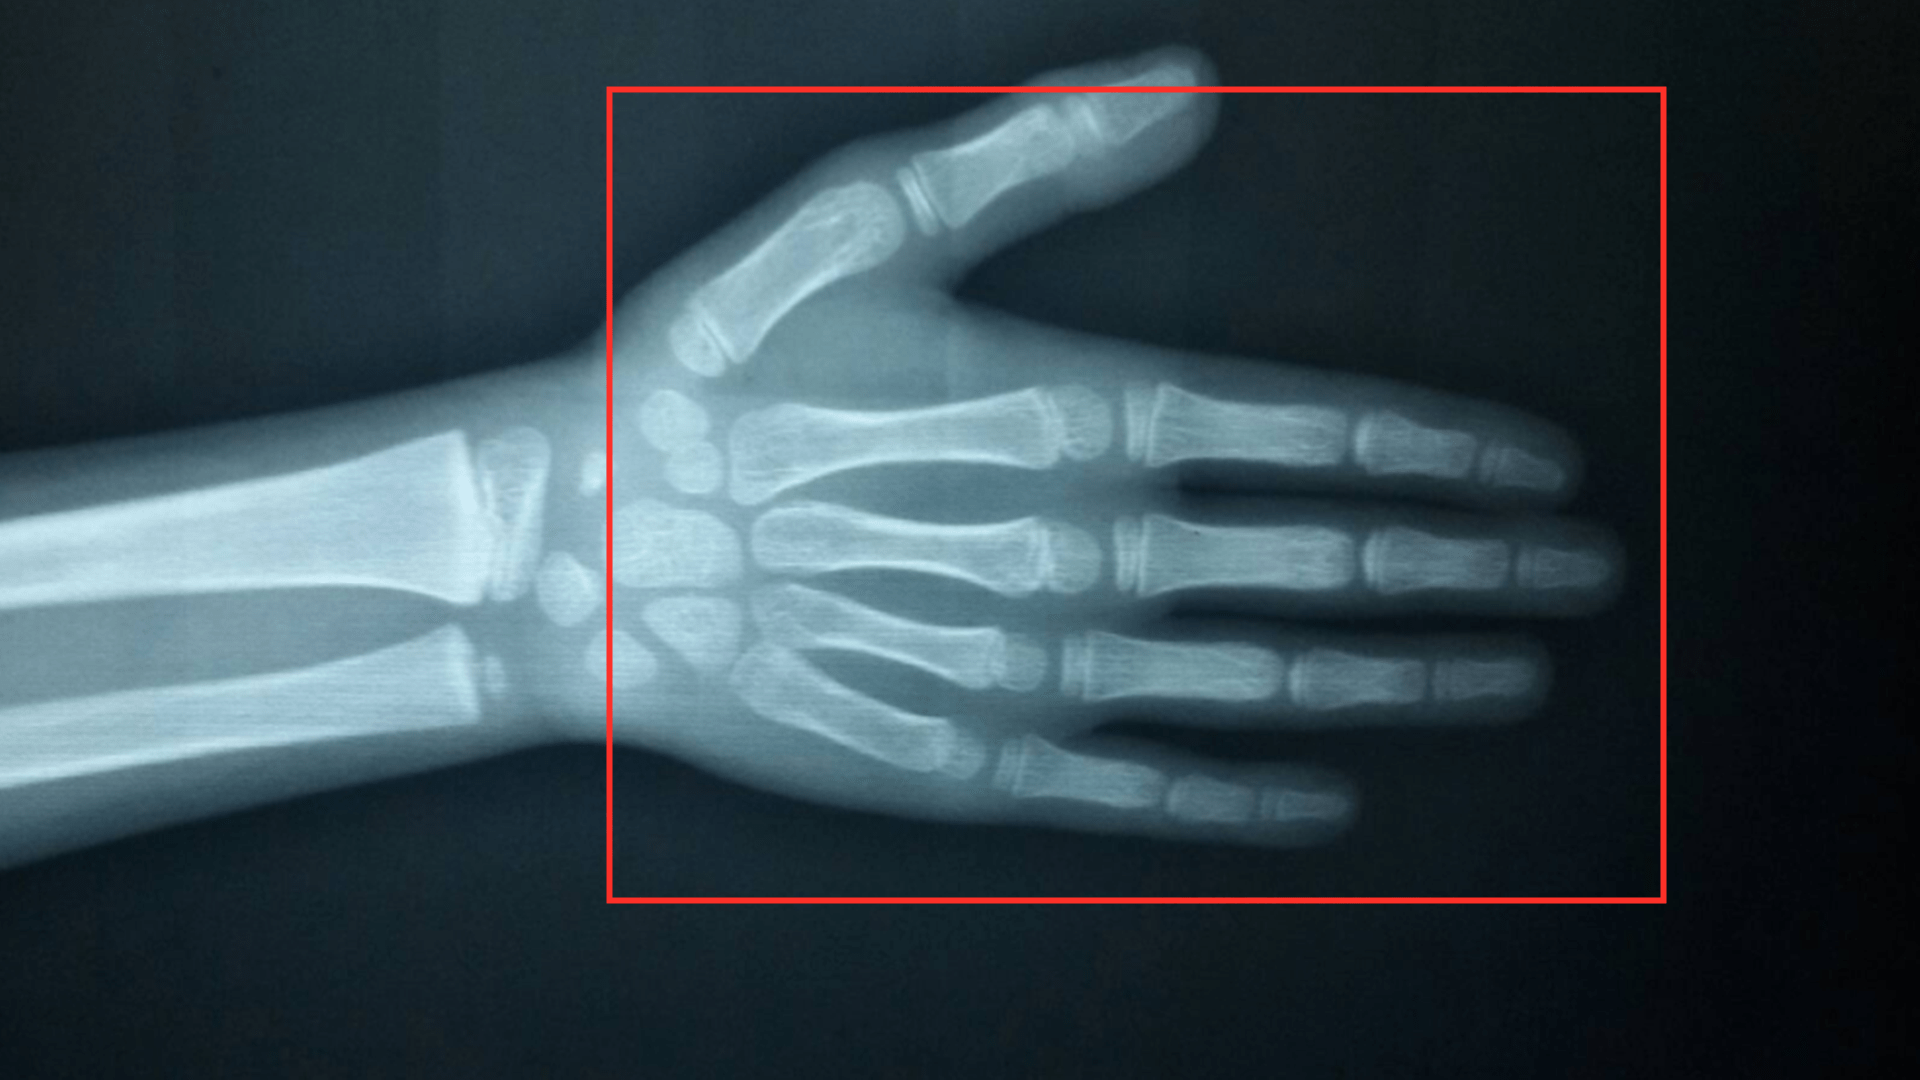

测骨龄

测骨龄一般用于身高异常的孩子 , 能够测算出还能够增长多少厘米 , 或者身高和骨龄是否吻合的一种方法 。 经过测骨龄 , 发现这孩子的身高最多的长高空进 , 仅有0.5-2厘米 , 也就是说 , 按照现在他160厘米的身高 , 最多只可能长到162厘米 。

但是 , 他的父母身高都比较高 , 按照遗传身高测算 , 他能够长到173厘米 , 这个结果让家长无法接受 , 后来经过医生的询问 , 谜底被揭晓 。